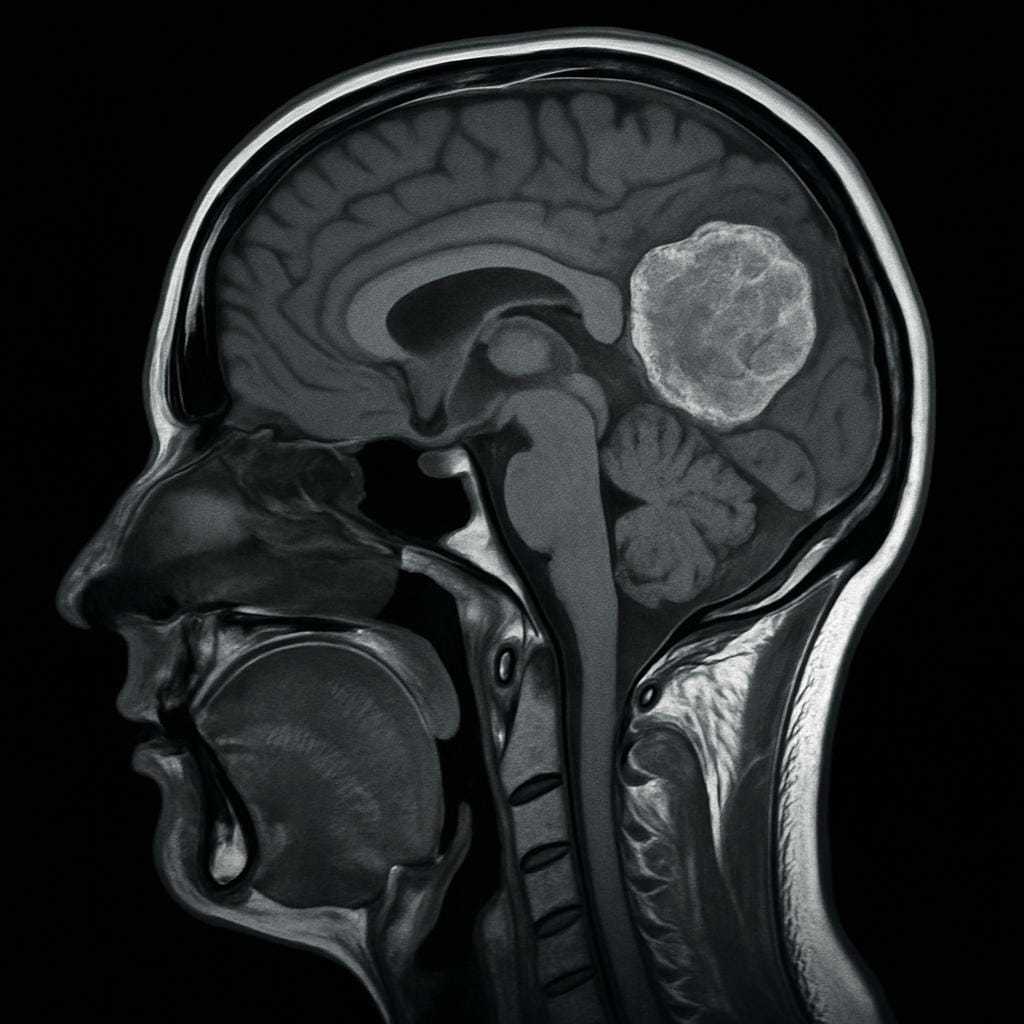

Tumores cerebrais são formações anormais de células dentro do crânio. Eles podem ser benignos (não cancerosos) ou malignos (cancerosos), e afetam o cérebro ou a medula espinhal. Mesmo os tumores benignos podem causar sintomas graves por pressionarem estruturas delicadas.

Tumores Cerebrais: Quais os Primeiros Sintomas Que Você Não Deve Ignorar